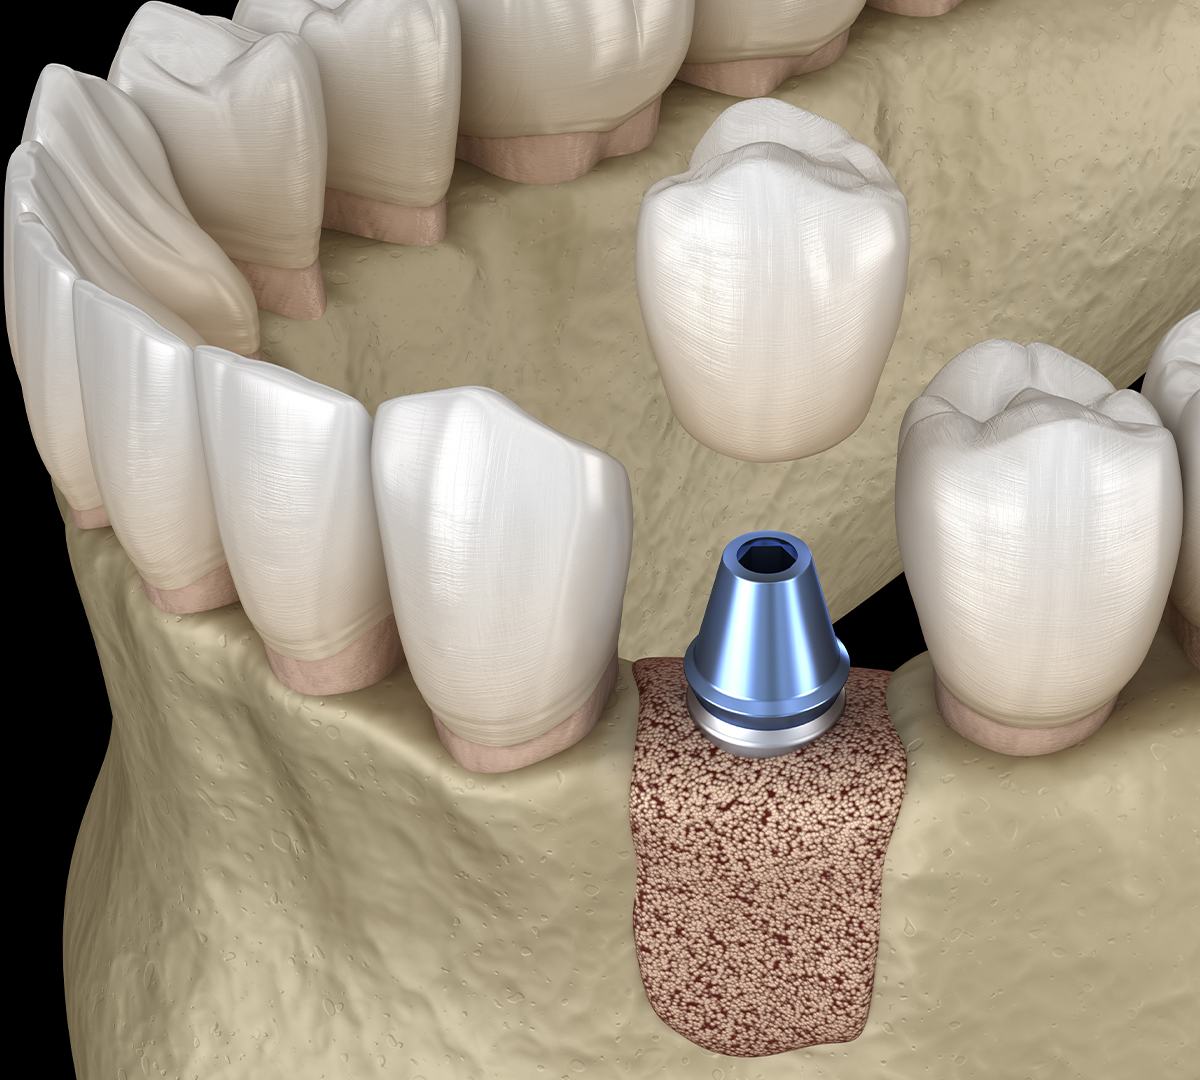

La greffe osseuse et la régénération osseuse sont des techniques chirurgicales permettant de restaurer l’os dans les zones où il a subi une perte significative. Ces interventions sont souvent nécessaires avant la pose d’implants dentaires, afin de garantir un support solide et une intégration optimale.

La greffe osseuse permet alors de recréer une base osseuse suffisante en augmentant la largeur et/ou la hauteur de l’os, garantissant ainsi une pose d’implant dans de bonnes conditions et en toute sécurité.

Déroulement d’une greffe osseuse

- Bilan clinique et radiologique pour évaluer la perte osseuse.

- Intervention chirurgicale sous anesthésie locale : la greffe est positionnée au niveau du défect osseux.

- Période de cicatrisation de quelques mois avant la pose de l’implant, pour permettre à l’os de se régénérer complètement.